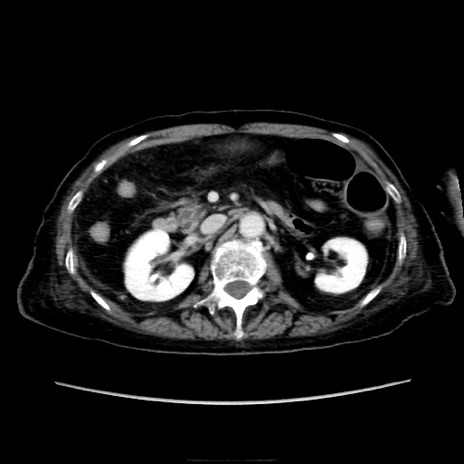

症例40(横断像)

【症例】90歳代女性

【主訴】腹痛・嘔吐

【現病歴】 食欲低下、嘔吐があり昨日他院受診。肺炎と診断され入院となる。入院後より腹部全体に圧痛あり。胃管留置され経過みていたが、症状持続するため、

当院転院となる。

【既往歴】胸椎圧迫骨折、胆石症

【身体所見】腹部:中央に激痛あり、圧痛あり、反跳痛不明

【データ】WBC 17100、CRP 18.82

横断像